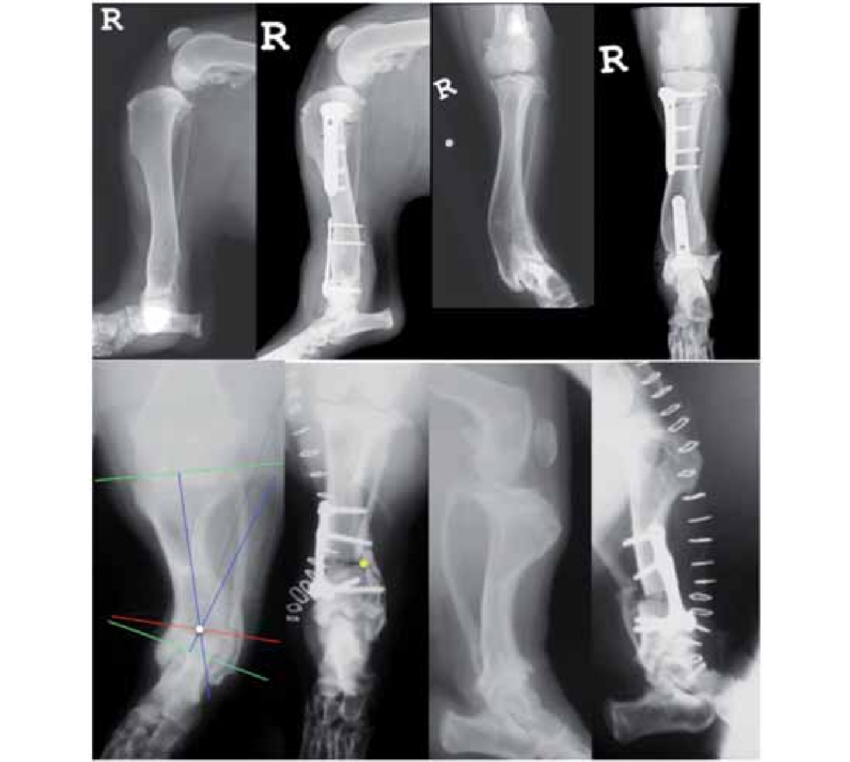

Figur 2 visar ett fall av proximal tibiafelunion behandlad med osteotomi och dubbelplattning. Figur 3 visar ett fall av proximal tibiamalunion behandlad med intraartikulär osteotomi.

hoppar över text

Fall av en 54-årig kvinna med intraartikulär (går in i leden)malunion av proximala tibia med 5 mm lateral depression och 13 graders varusdeformitet (första bildraden). CT-skanning visas i den andra bildraden. Patienten behandlades med en lateral parapatellär metod med en lateral tibial tuberkelosteotomi och en falluckosteotomi. De deprimerade fragmenten lyftes följt av en öppningskils tibialosteotomi. Mediala och laterala plattor applicerades för att hålla repositionen (tredje bildraden).

En posterior metod användes för att avlägsna fibrös vävnad och mobilisera det felaktigt förenade fragmentet. Ledkongruensen återställdes och fixationen säkrades med en posterior stödplatta och dragskruvar.

kvarvarande depression av den laterala tibialplatån eftersom den hade korrigerats framgångsrikt med den ursprungliga operationen.